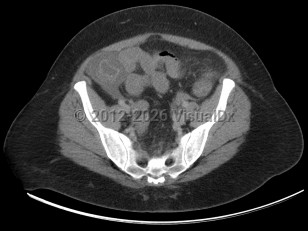

Neutropenic enterocolitis

Patients with leukemia undergoing cytotoxic chemotherapy are at highest risk for neutropenic enterocolitis. This was initially appreciated in pediatric patients but is seen in adults as well. Any patient with chemotherapy-induced neutropenia is at an increased risk for neutropenic enterocolitis.

Neutropenic enterocolitis commonly presents with right lower quadrant abdominal pain, diarrhea, and fever with underlying neutropenia or immune compromise. Patients can develop severe sepsis with end-organ damage and bowel perforation with progressive neutropenic enterocolitis. Early recognition and treatment of sepsis with intravenous antibiotics and volume resuscitation, along with surgical intervention if necessary, are the hallmarks of treatment that can improve mortality. If untreated, neutropenic enterocolitis can be fatal.